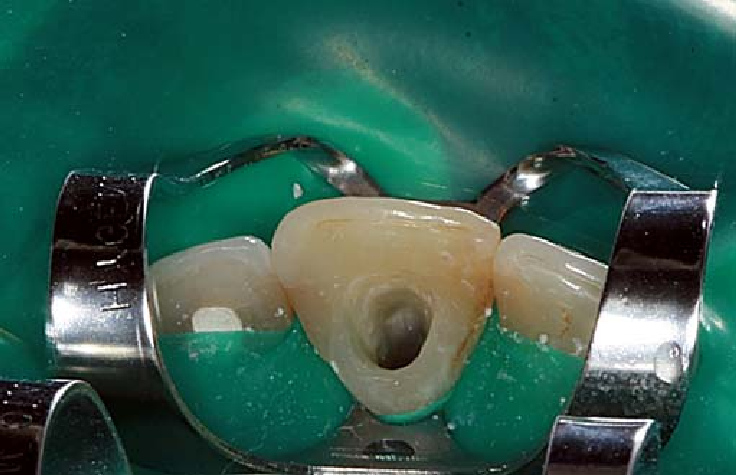

Wortelkanaalbehandelingen